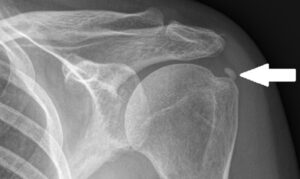

Osteólisis de Clavícula

En algunos casos la causa de inflamación no es una simple inflamación, sino que se debe una erosión de clavícula o una degeneración de la articulación acromioclavicular (artrosis acromioclavicular). En estos casos utilizamos una técnica quirúrgica que ofrece altas tasas de curación que consiste en resecar de 5 a 10 mm de la punta de clavícula para evitar el roce (cirugía de Munford).